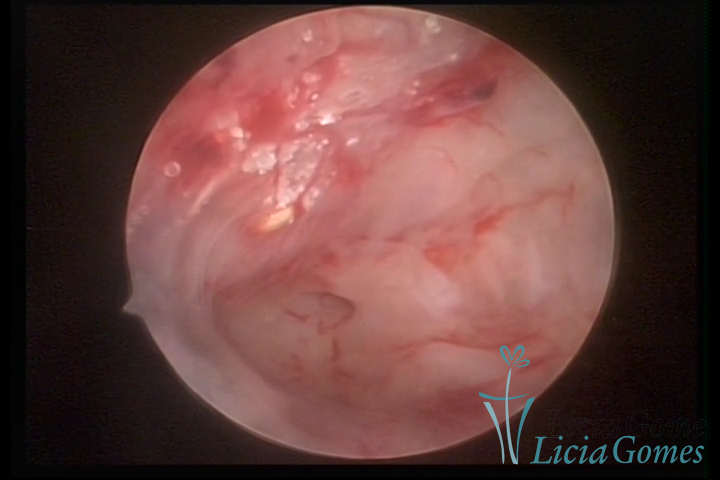

Metaplasia óssea: pontilhado esbranquiçado com calcificações

etaplasia óssea: pontilhado esbranquiçado com calcificações

Metaplasia óssea e lesão de adenomiose

METAPLASSIA ÓSSEA